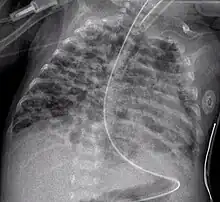

Projectionally rendered CT scan, showing the transition of thoracic structures between the anteroposterior and lateral view Chest film showing increased opacity in both lungs, indicative of pneumonia

Chest film showing increased opacity in both lungs, indicative of pneumonia A chest radiograph showing bronchopulmonary dysplasia.